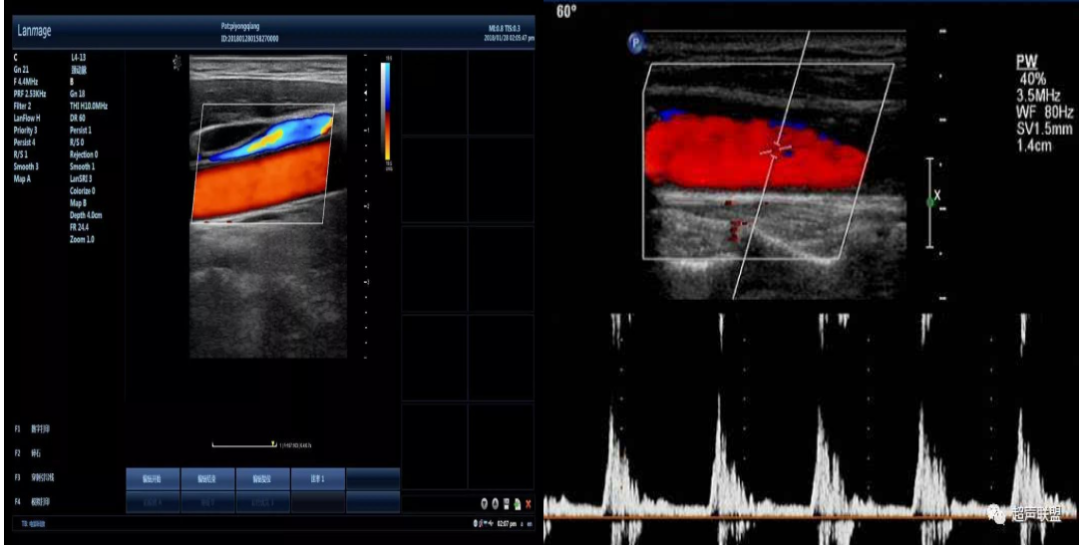

彩超血流的特点是颜色代表血流的方向,即红色代表血流方向朝向探头,蓝色代表血流方向背离探头;色调的亮度表示速度,即色调的亮度越亮表示速度越高,色调的亮度越暗表示速度越低;血流颜色的单纯代表是层流,是正常的血流。五彩镶嵌的花色血流信号代表是湍流或涡流,说明血流性质有改变,多见于狭窄处的血流以及返流。

2.可以动态显示血流的运行方向,方便了解血流的时相和速度。

3.可以辨别动脉和静脉血管,可识别血管性病变和非血管性病变

,可以了解血管的性质,可进一步鉴别良恶性肿瘤有帮助。

7.适用于颈部血管、四肢血管、腹部大血管——动脉粥样硬化伴斑块形成、锁骨下动脉盗血综合征、动脉瘤、静脉血栓、动静脉瘘、静脉瓣功能不全等) 。